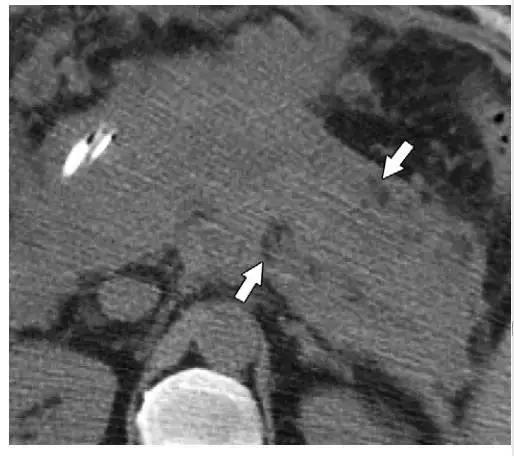

ANCs 也含有大量液体,和 APFCs 的鉴别是 ANCs 含有非液性成分,比如实性成分或脂滴。如果有碘对比剂禁忌证,平扫 CT 如果能发现脂性密度对确定坏死及诊断 ANCs 具有重要帮助(图 9)。

图 9 41 岁急性胰腺炎女性患者合并 ANC。发病 9 天后的 CT 平扫图像示胰腺和胰周密度对比度下降,因此难以确定胰腺实质坏死部位。但小脂滴(箭头)的出现和整体不均质密度均提示该患者为坏死性胰腺炎伴 ANC